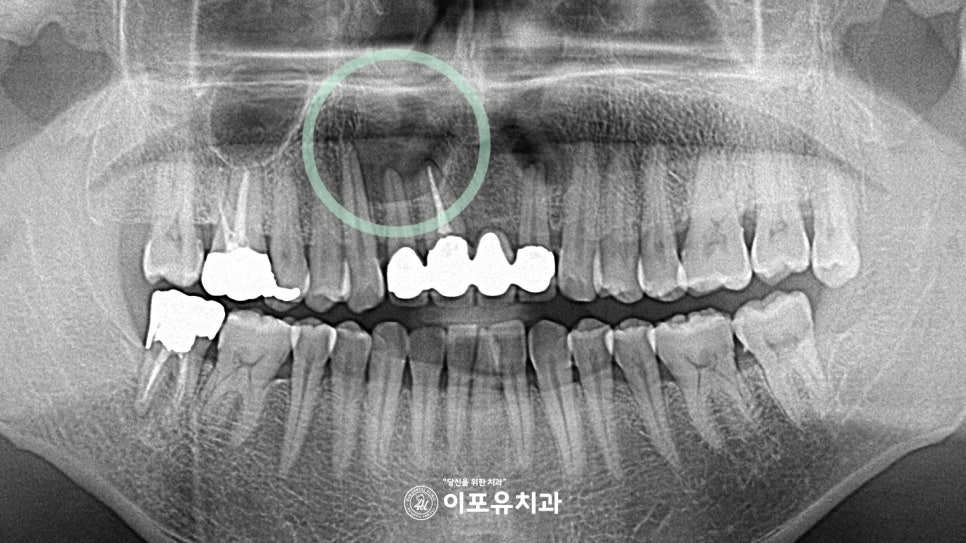

“전치부에 치아에 잡혀 있는 고름“

준비한 초진 사진을 살펴보면

굉장히 큰 크기의 병소가 관찰됩니다.